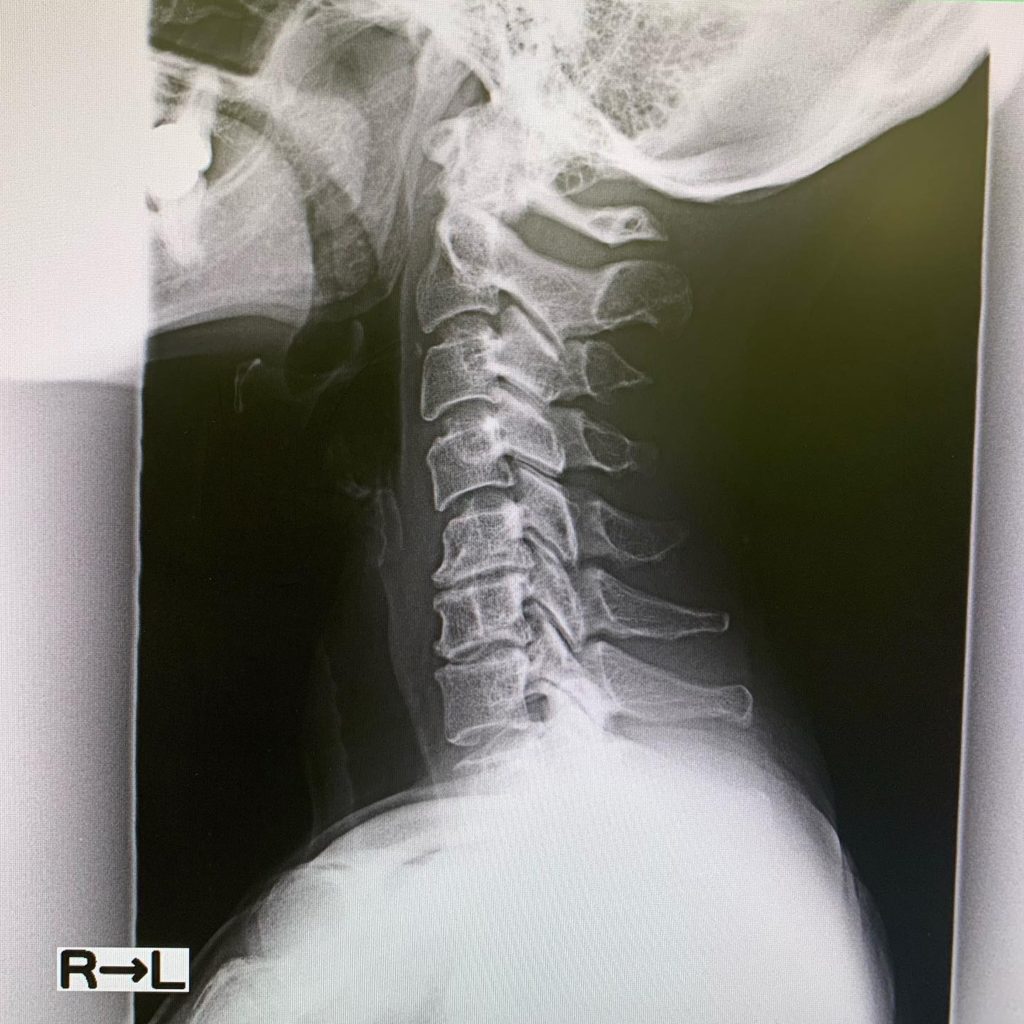

レントゲン撮ったら、首は真っ直ぐ過ぎるし、椎体は骨棘できて変形してるし、椎間板も減ってるし。